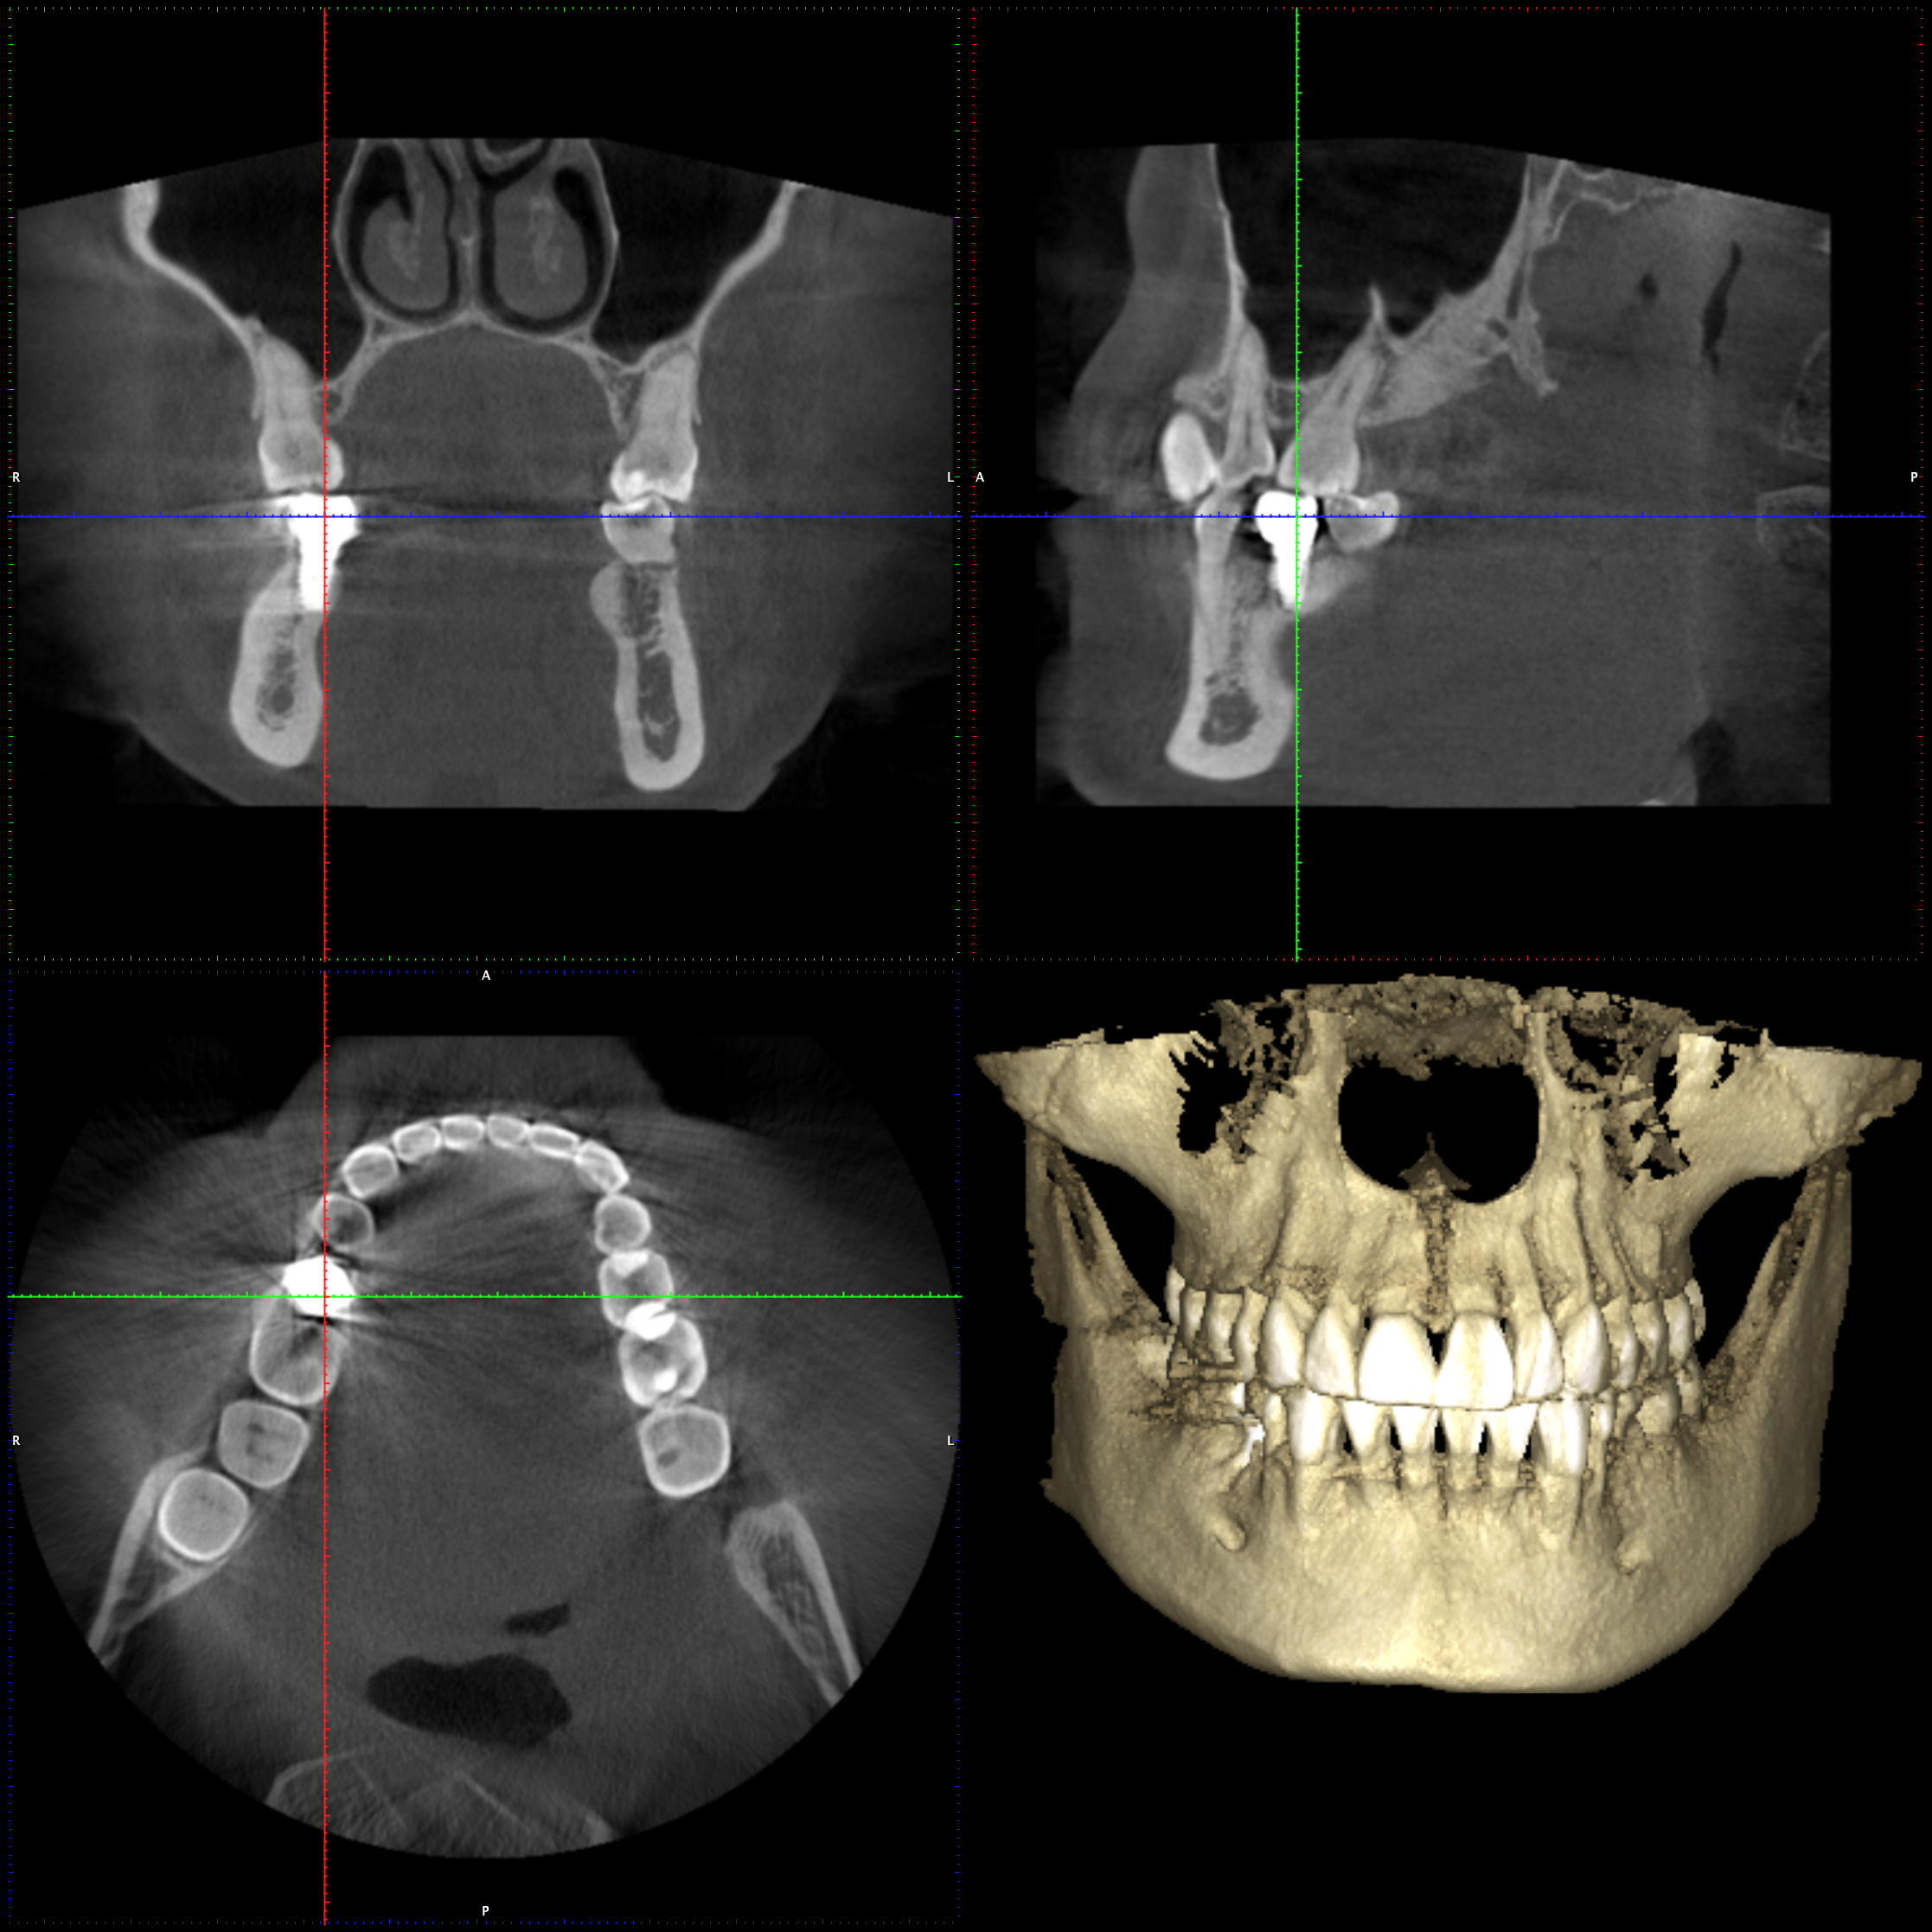

En PROTAC conseguimos una combinación ideal de calidad de imagen y usabilidad de alto nivel, ya que disponemos de una unidad CBCT(Cone Beam Computed Tomography) de última generación que supone un extraordinario avance en la evolución del procesamiento de imágenes de haz cónico, obteniendo una calidad de imagen optimizada, reduciendo los artefactos y garantizando imágenes de mayor contraste, para conseguir así satisfacer las necesidades del exigente procesamiento de imágenes maxilofaciales en todos los entornos clínicos. Nuestro innovador software Planmeca Romexis® ofrece herramientas especialmente diseñadas para especialistas en implantología, endodoncia, periodoncia, prostodoncia, ortodoncia, cirugía maxilofacial y otorrinolaringología.

Nuestra unidad de escáner y radiografía dental y nuestro software de procesamiento de imágenes brinda una combinación innovadora de imágenes 2D y 3D que le ofrecen una visión más completa para conocer con mayor exactitud las necesidades de sus pacientes.

Unidad CBCT de última generación con una calidad de imagen optimizada.

Software con herramientas especializadas para implantología, endodoncia, periodoncia, prostodoncia, ortodoncia, cirugía maxilofacial y otorrinolaringología.

Imágenes 2D y 3D más completas para conocer con mayor exactitud las necesidades de sus pacientes.